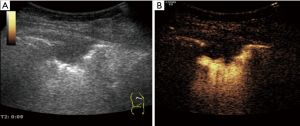

The arterial phase was determined by comparing contrast agent AT in the peripheral lung lesion with that in adjacent lung tissue using “real-time comparative observation method” (12). All patients underwent percutaneous peripheral lung lesion biopsy under traditional ultrasound or CEUS guidance paying attention to avoiding necrotic areas and large blood vessels (Figure 1). All the specimens were examined pathologically. None of the patients had contraindications for CEUS and the biopsy, and signed informed consent was obtained from each patient or family members before the CEUS and biopsy procedures.

Total of 92 peripheral lung lesions were note with mean diameter of 3.2±1.1 cm (range, 1.2–9.2 cm), including 39 small lesions with a diameter of 1–2 cm and 53 large lesions with a diameter greater than or equal to 2 cm. All 92 lesions had either uniform or inhomogeneous hypoechogenicity on gray-scale ultrasound, 79 lesions were hypovascular and 13 lesions were hypervascular on Doppler imaging. Fifty-two patients were performed percutaneous biopsy by CEUS guidance and 40 patients were performed by traditional ultrasound guidance. Of 52 lesions by CEUS guidance, 27 (51.9%) showed non enhanced necrosis areas on CEUS and only 5 of them showed liquefaction necrosis areas on gray-scale ultrasound, a large narrow base lesion sized 3.5cm for high risk of pneumothorax was ignored on gray-scale ultrasound and discovered by CEUS preprocedure, the other 51 lesions displayed with wide base on gray-scale ultrasound and CEUS (Figures 3,4). Of 40 lesions by traditional ultrasound guidance, 4 showed liquefaction necrosis areas on gray-scale ultrasound.